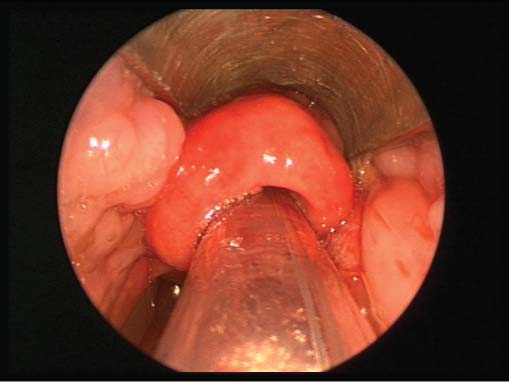

Epiglottitis is a serious medical condition that occurs when the epiglottis, a flap of cartilage located at the base of the tongue, becomes inflamed and swollen. This can lead to difficulty breathing and swallowing, which can be life-threatening if left untreated.

Epiglottitis is usually caused by a bacterial infection, most commonly Haemophilus influenzae type b (Hib) bacteria. The infection can lead to swelling and inflammation of the epiglottis, making it difficult to breathe and swallow.

Other causes of epiglottitis include viral infections, fungal infections, and trauma to the throat.